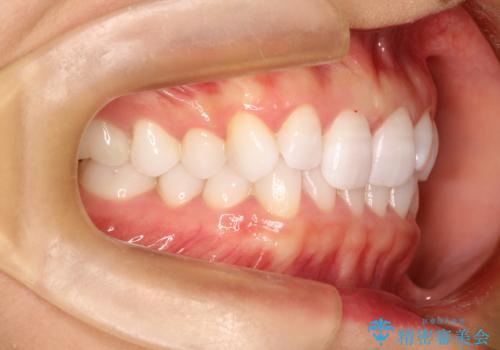

気になる前歯の歯並びをインビザラインで矯正

- 前歯の傾きと、ガタガタが気になるとのことで来院されました。

アスリートの方でしたので、競技に支障が少ないインビザラインで治療することとなりました。

前歯の傾きや高さをシミュレーションで患者様と確認しながら、歯並びを仕上げていきました。